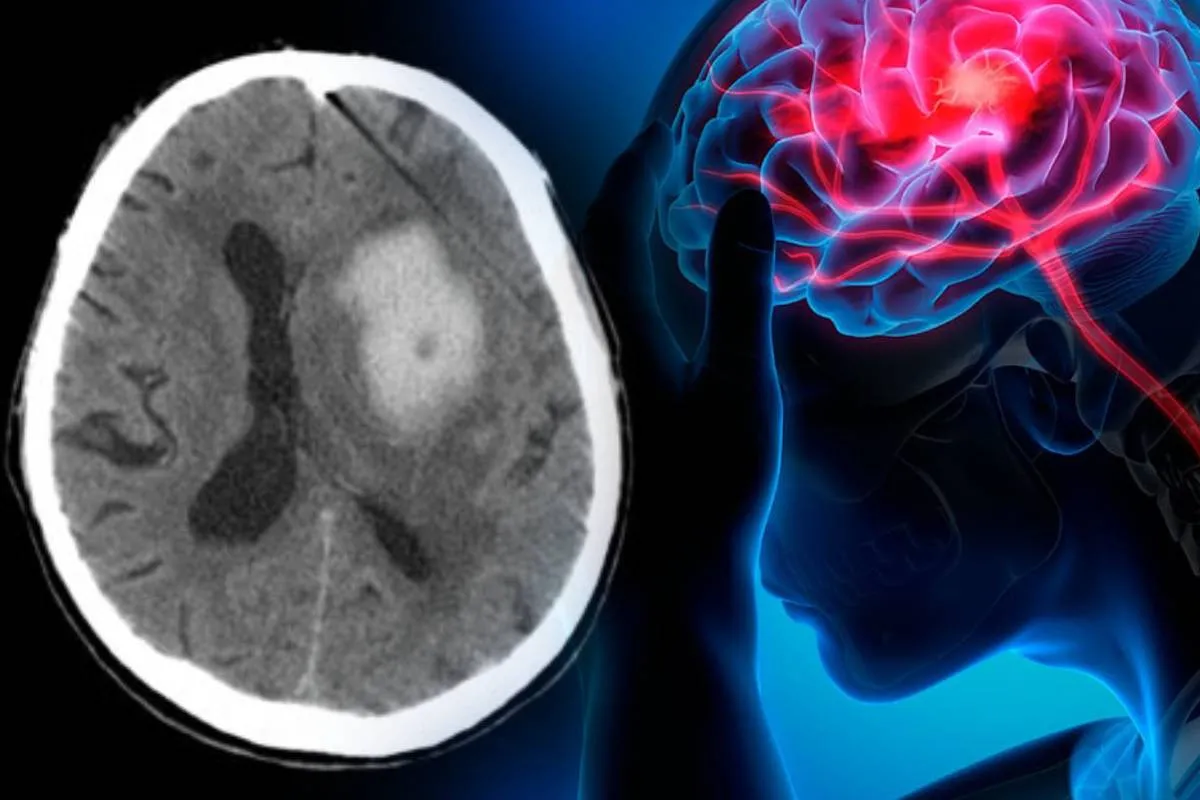

Существует два типа инсультов — ишемический и геморрагический. Причиной ишемических инсультов являются тромбы, которые блокируют кровоток в сосудах мозга. Геморрагический инсульт возникает из-за разрыва сосуда и, как следствие, кровоизлияния в мозг.

Как отмечает профессор сердечно-сосудистой медицины и почетный консультант-кардиолог Шеффилдского университета Тим Чико, стресс, вызванный войной, повышает риски возникновения обоих типов инсультов. По словам медика, из-за значительного стресса в организме могут возникать тромбы, которые в конечном итоге становятся причиной инфарктов и инсультов.

Постоянные обстрелы и авиаудары существенно усложняют предоставление экстренной медицинской помощи в прифронтовых регионах. Поэтому нередко драгоценное для выздоровления пациентов время тратится на дорогу до медицинского учреждения. Как объясняет Наталья Некрасова, решающими при инсульте являются первые пять часов с момента его возникновения. Этот период называют “золотым окном”. Именно в это время еще возможно растворить тромб без значительных последствий для мозга.